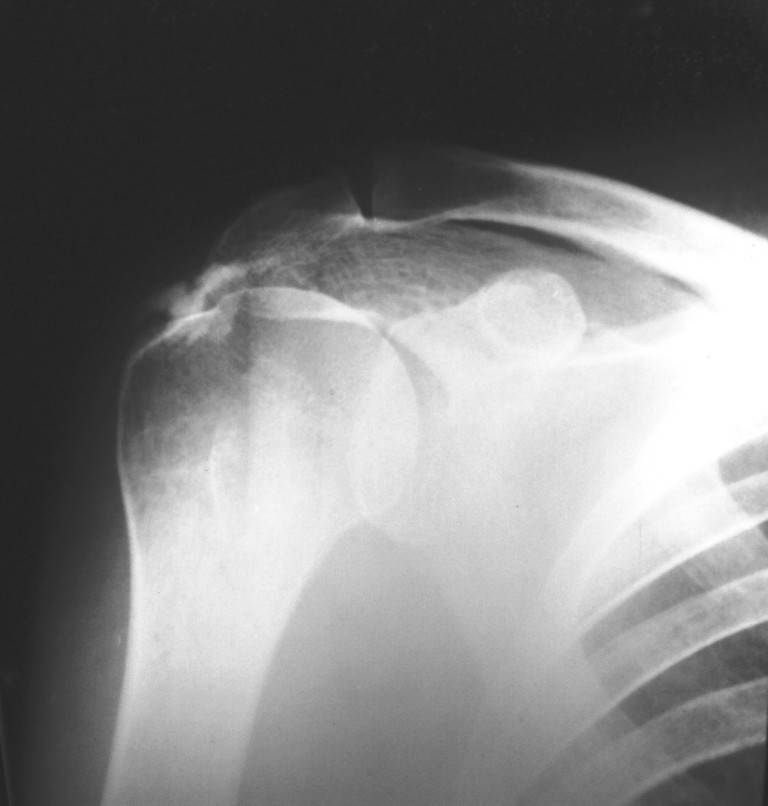

"Жалоб на функцию правого плечевого сустава не предъявляет, движения в полном объеме, активные и пассивные без ограничений и боли.снимок был проведен с целью контроля состояния сустава, так как больная в 2003 году проходила у меня лечение по поводу правостороннего осифицирующего тендинита надостной мышцы." - все таки непонятно, с какой целью сделана рентгенография, и были ли ли для нее показания. К сожалению снимок не позволяет что либо судить конкретно (скорее всего качество потеряно при переформатировании). Конечно желательно бы разместить старые и свежие снимки хорошего качества.

Снимок проводился с целью контроля. Больная обратилась по поводу аналогичного процесса только в левом плече. Я попросил сделать снимок также и правого сустава, так как лечил её в 2003г. с аналогичным диагнозом, но только с правой стороны.

По поводу качества я согласен, но я не могу заставлять больную платить деньги за снимки сделанные на качественном оборудовании, если она может сделать бесплатно в поликлинике...

По вашей просьбе размещаю снимок 2003г.